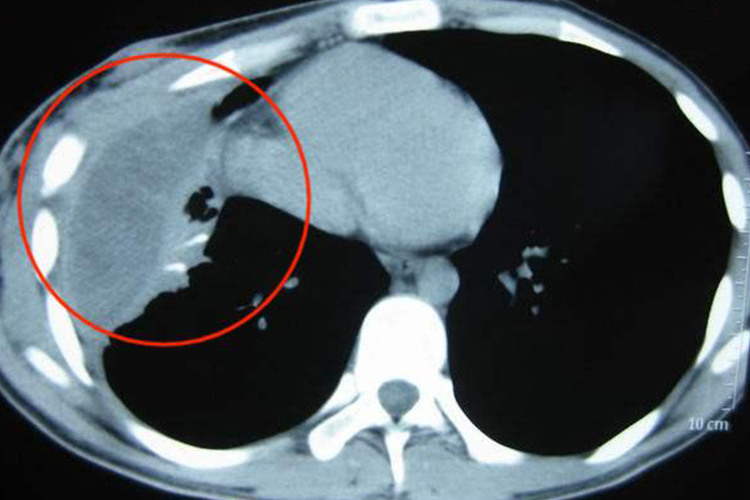

化脓性胸膜炎:化脓性胸膜炎的胸腔积液密度较一般渗出性胸腔积液的密度稍高,部分可见气体影,脓胸的壁厚而较均匀,邻近的肺实质受压移位。增强CT显示脓腔壁呈明显环状均匀强化,内壁光滑。